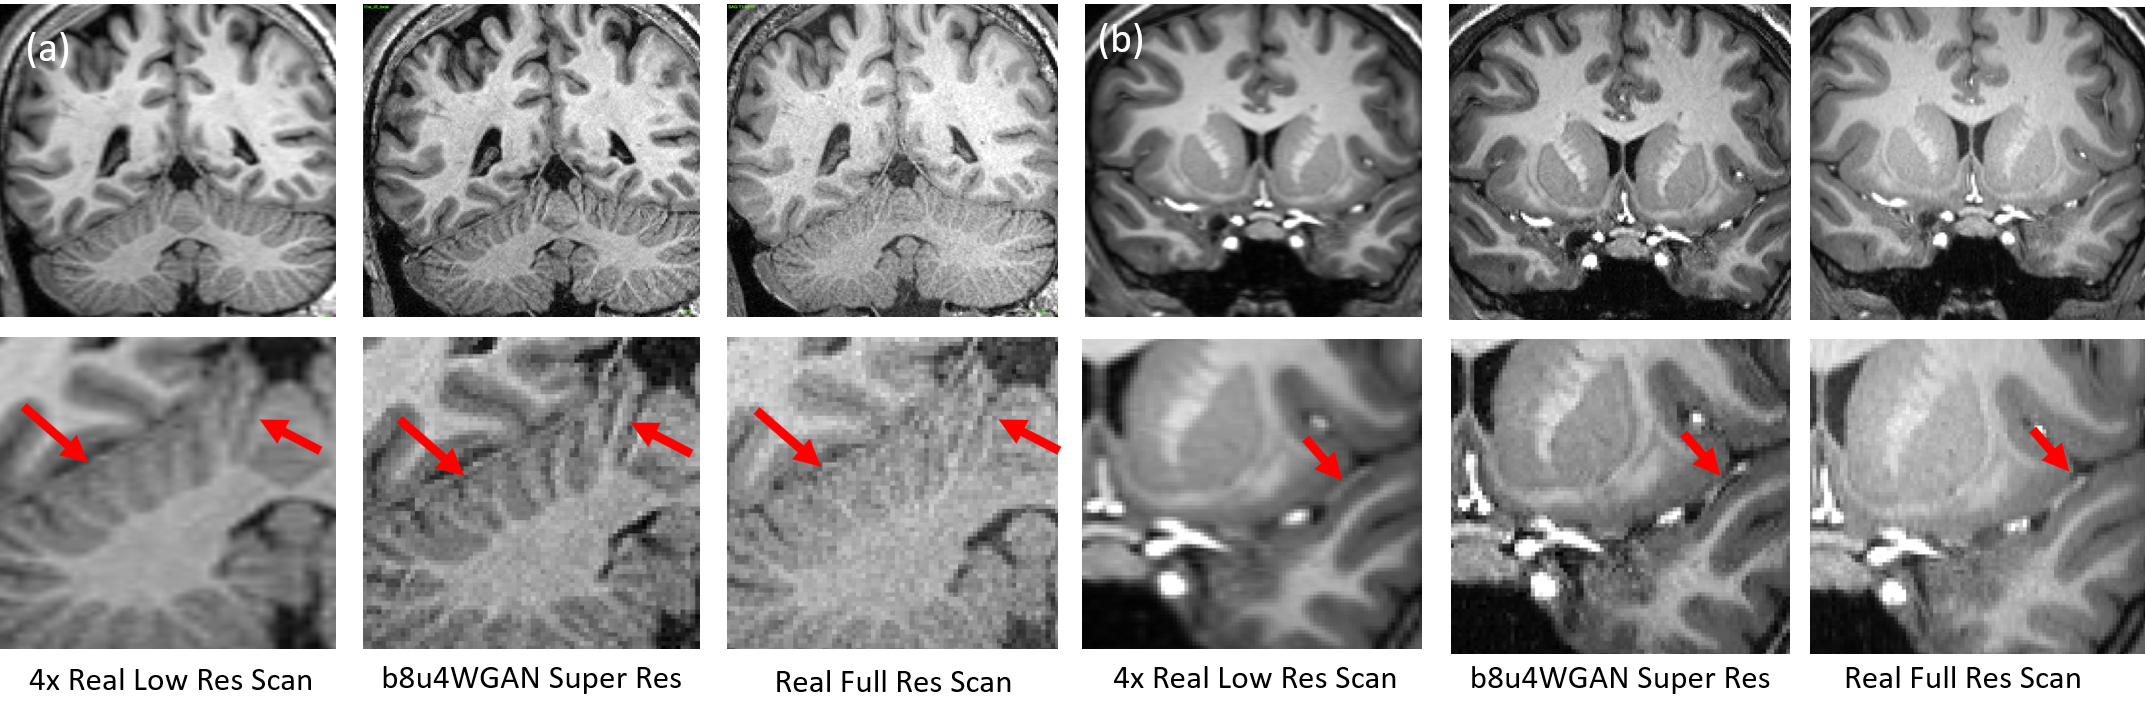

Figure 8: Two real-world examples are shown in 2×2222\times 2 resolution-reduced plane. There are slight mismatches between LR and HR, because they are from two separate scans. These scans were done on a different version of Siemens MRI scanner at Cedars-Sinai Medical Center. mDCSRN-GAN provides a comparable image quality to high-resolution scan.

Prospective MR Scans. Additionally, we also performed a real-world test on seven volunteers in our on-site 3T Siemens Verio MRI scanner, which is different to those Prisma scanners utilized in the HCP dataset. We followed the same protocol as in Van Essen et al. (2013) except for reducing the phase encoding and slice resolution by half, which effectively reduced spatial resolution by 4x. As shown in Fig. 8 and Table 4, the mDCSRN-GAN model showed excellent ability in recovering edge details that hardly seen in the fast low-resolution scan. Besides noticeable sharpness improvement, the SR output seems to have a lower noise level and cleaner image than the original full-resolution scan because of the low-resolution image that has a better SNR than HR. It’s an extra gain from super-resolution techniques in addtion to the time- and cost-saving. As the real scan was performed on a completely different machine on a different site and subject, the noise pattern and image quality were considerably different than the training dataset. It displays our model’s robustness and performance in a real-world scenario.